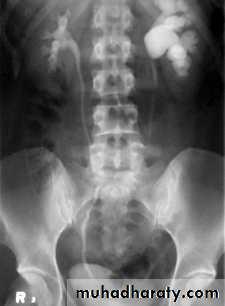

Poly cystic disease

Adult type

Present after the third decade of life , Familial.

Renal parenchyma is replaced by numerous cysts containing fluid , The cysts are of variable size ,

Clinically renal colic, loin mass , heamaturia and hypertension, Renal tissue interposed between the cysts after time dssimcted ended with renal failure

Almost bilateral.

IVU

Large kidney .

Lobulated out-line.

Distortion of pelvi- calyceal system depend on cyst size, number and position.

In advanced cases there is elongation and stretching of minor and major calyces ( spider leg).

In advanced cases IVU shows non-functioning kidney .